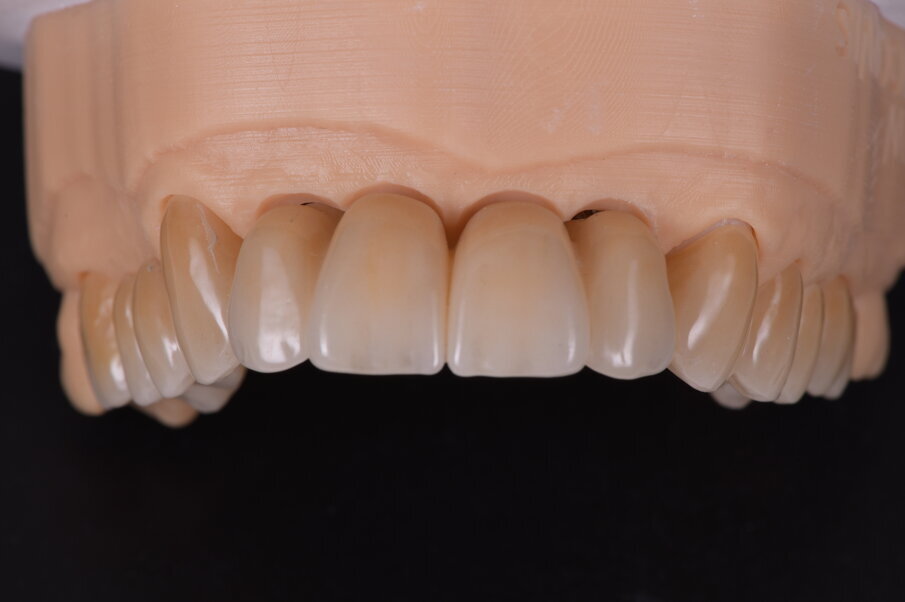

Fig. 33_Modelli realizzati in resina e montati in articolatole a valori medi.

Fig. 34_Dettaglio del modello superiore con la visione palatale, con i monconi t-base da ancoraggio per elementi CAD/CAM.

Fig. 35_Sovrapposizione di un’immagine stilizzata degli elementi realizzabili con un margine muso ricreato.